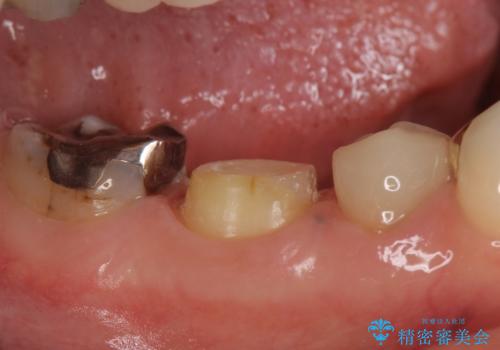

- 右下でものを咬むと歯茎が疼くので診て欲しいといらっしゃった方の症例です。

診査の結果右下6の歯の神経が死んでいたため、根管治療を行いました。

その後症状の消失を確認し、オールセラミッククラウンによる補綴を行いました。